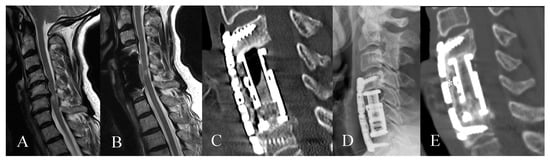

2. Materials and Methods

3. Results

3.2. Radiological Outcome